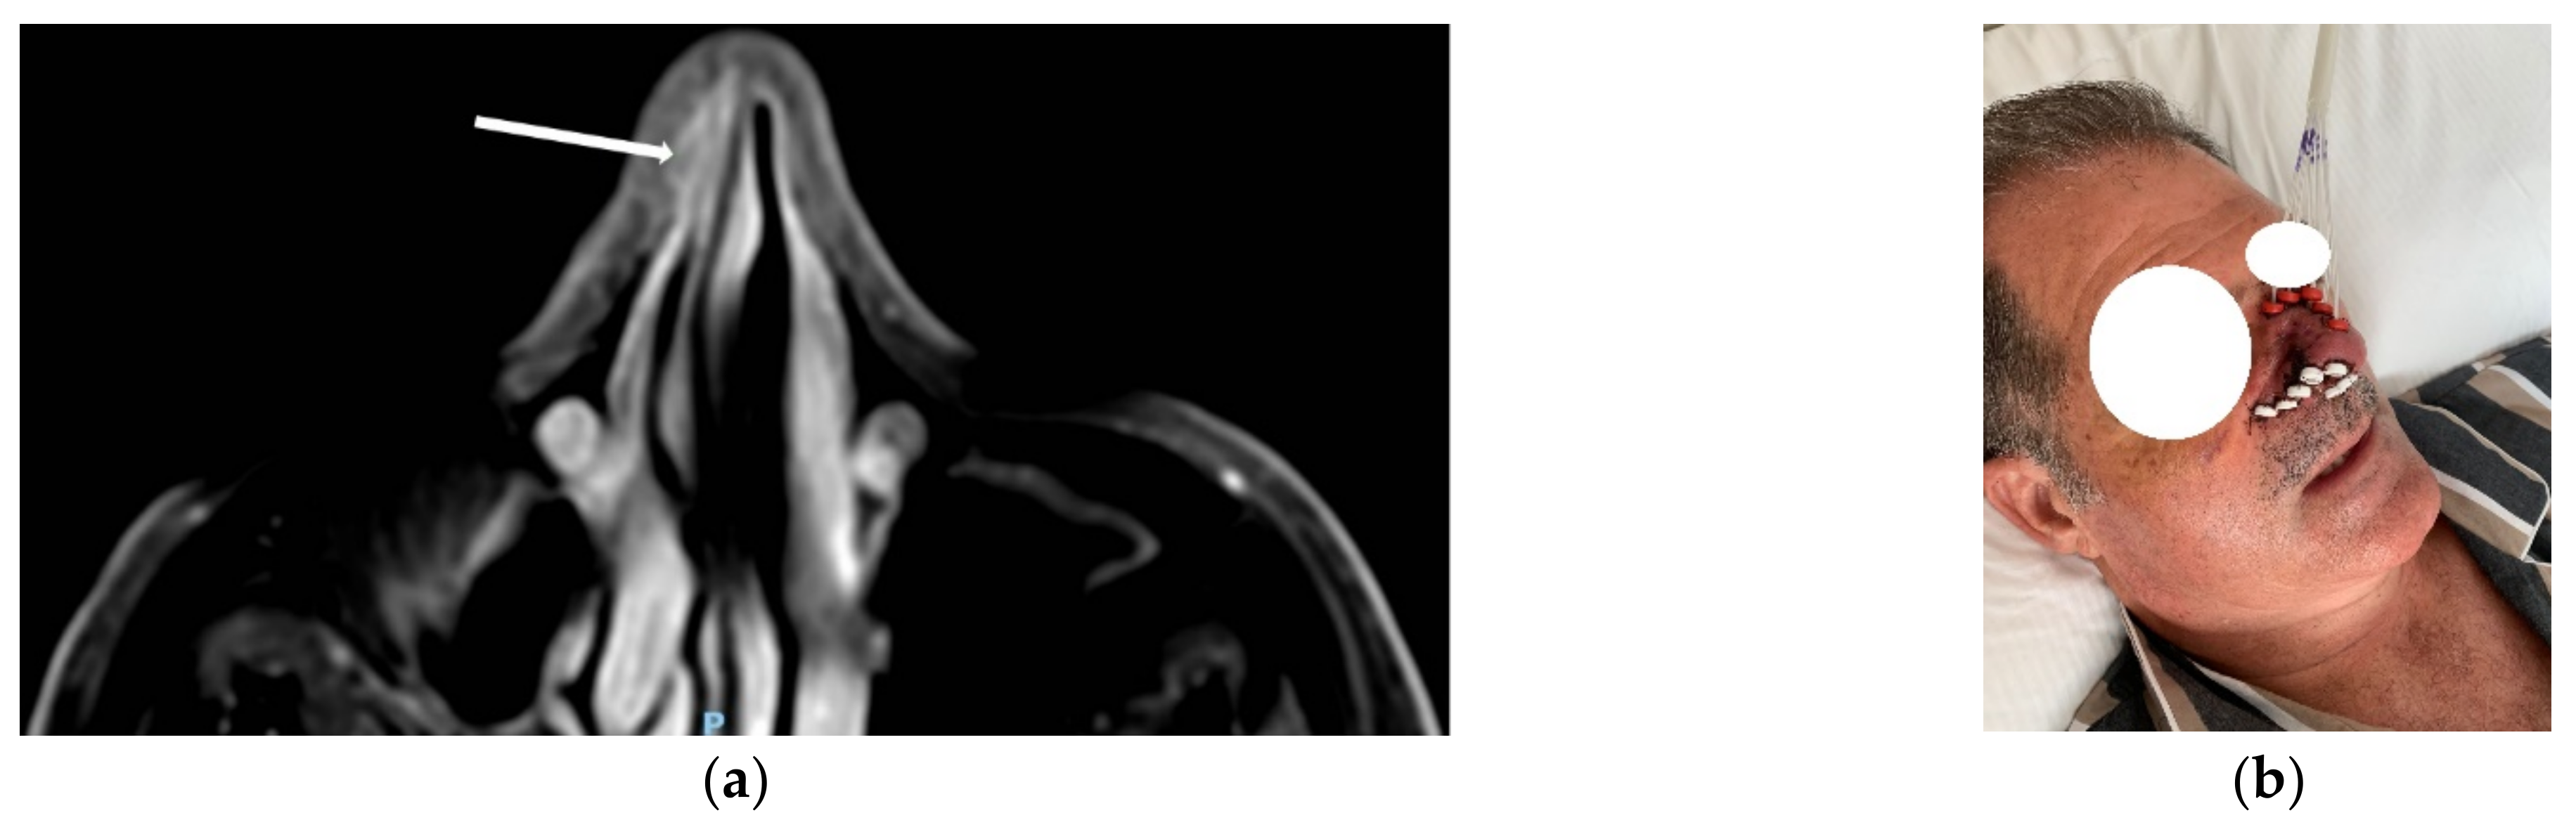

| a. CT or MRI to define the ideal position and insertion of the catheters |

| b. CT-based pre-planning |

| a. CT definition of the actual catheter position for 3D treatment planning |

| b. CT-based IRT planning and optimization |